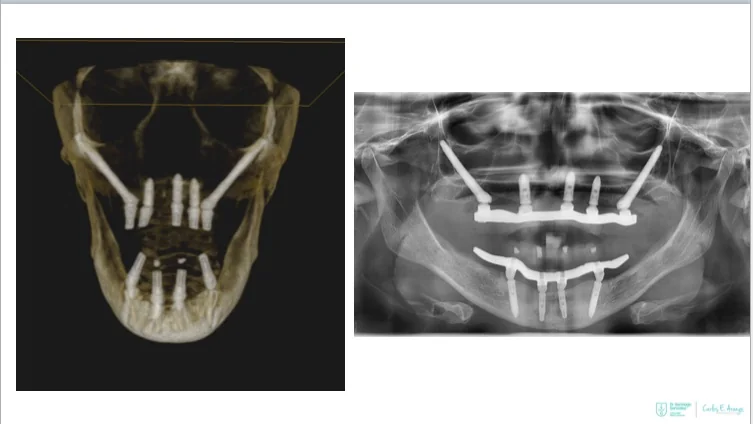

- Full-arch rehabilitation with only four implants

Two straight anterior implants and two implants tilted up to 45º in the posterior - Immediate Function (fixed provisional bridge)

For patients meeting criteria for immediate loading of implants - Graftless Procedure: Bone grafting is avoided by tilting the posterior implants, utilizing available bone.

Smile Again: Full mouth dental implants

Four implants can replace all of the teeth on the top or the bottom! Dental implant technology advances have paved the way for innovative new solutions.